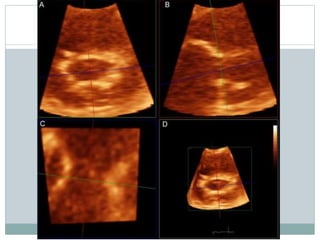

2D ECHO

 Commissural fusion

PSAX echo scanning of valve

Important in distinguishing

degenerative from rheumatic

valve

Complete fusion indicate

severe MS

Narrow diastolic opening of